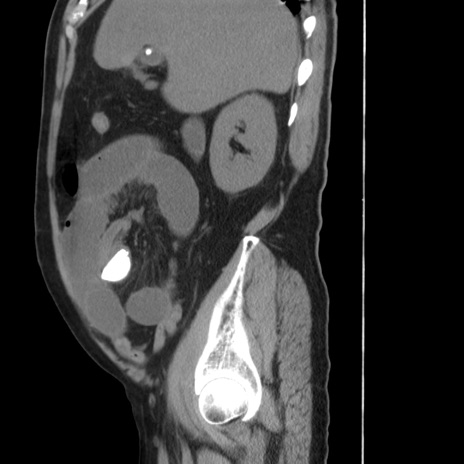

症例20(矢状断像)

【症例】 60歳代男性

【主訴】 腹部膨満、嘔吐

【現病歴】5日前頃より倦怠感を認め食事量減少し4日前の朝嘔吐、食事摂取困難となった。 3日前近医受診し点滴施行され整腸剤などを処方された。 当日他院を受診し、腹部膨満著明、炎症反応の上昇(CRP10.8、WBC11200)あり、紹介受診となる。

【身体所見】 意識JCS1 受け答えがはっきりしないBP 111/57mHg、 P 67bpm、、BT35.2°C、SpO2 97%(RA)、 腹部:膨隆、打診で鼓音あり、全体的に圧痛有り、腸蠕動音(-)、反跳痛ははっきりせず。

【データ】WBC 11400、CRP 14.20